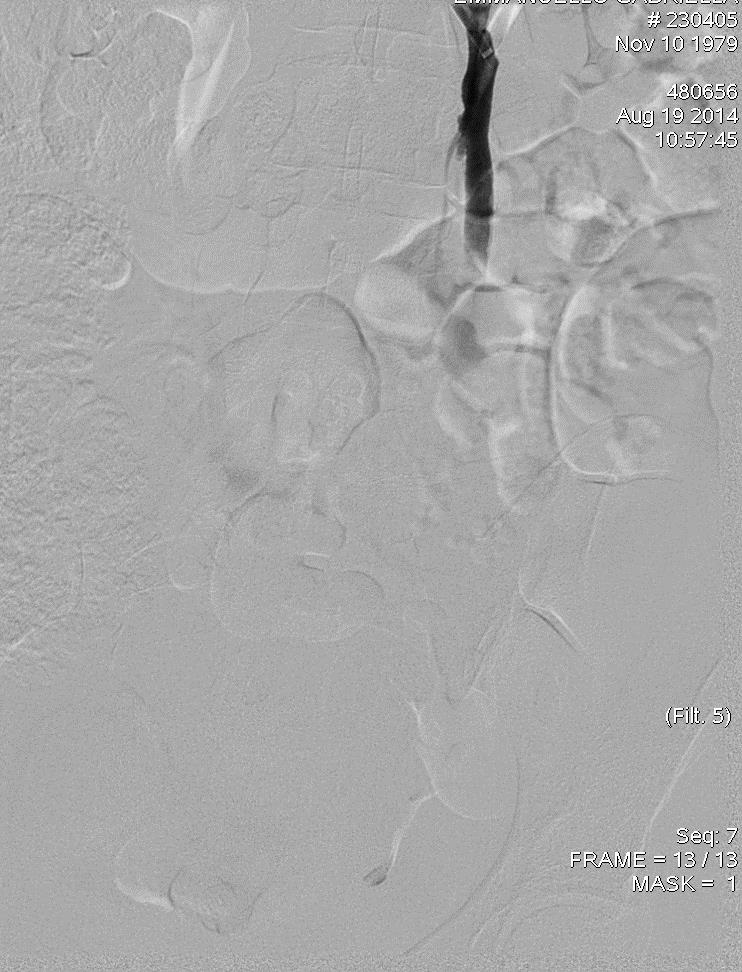

Embolization of Ovarian Vein Varices

Embolization 材料包括

• Coils

• Sclerosing agent

• Glue

• Combination

1: Coïls only 2: Coïls + Foam 3: Coïls + Onyx

No. Coil 7.2 coils (2-21), 4 coils (1-15), 4 coils (2-10)

Average time procedure > 60 min < 45 min 60 min

Transitory pelvic pain (< 48 h): 5% 5% 2%

Transitory variation of temperature (38°C): yes yes -

Pain during the procedure 1 % 12 % (spasm and foam) 100 %(DMSO)

Bad Breath (Smell of garbit during 2 days): - - yes

migrating coils (without consequence) 2 1

pulmonary embolismce): (without consequence) 1 1

vision trouble (foam)q   1

Recurrence of SCP and/or SCVI(follow up) 8 % at 9 years 3 % at 5 years too short

cost the same the same more expensive